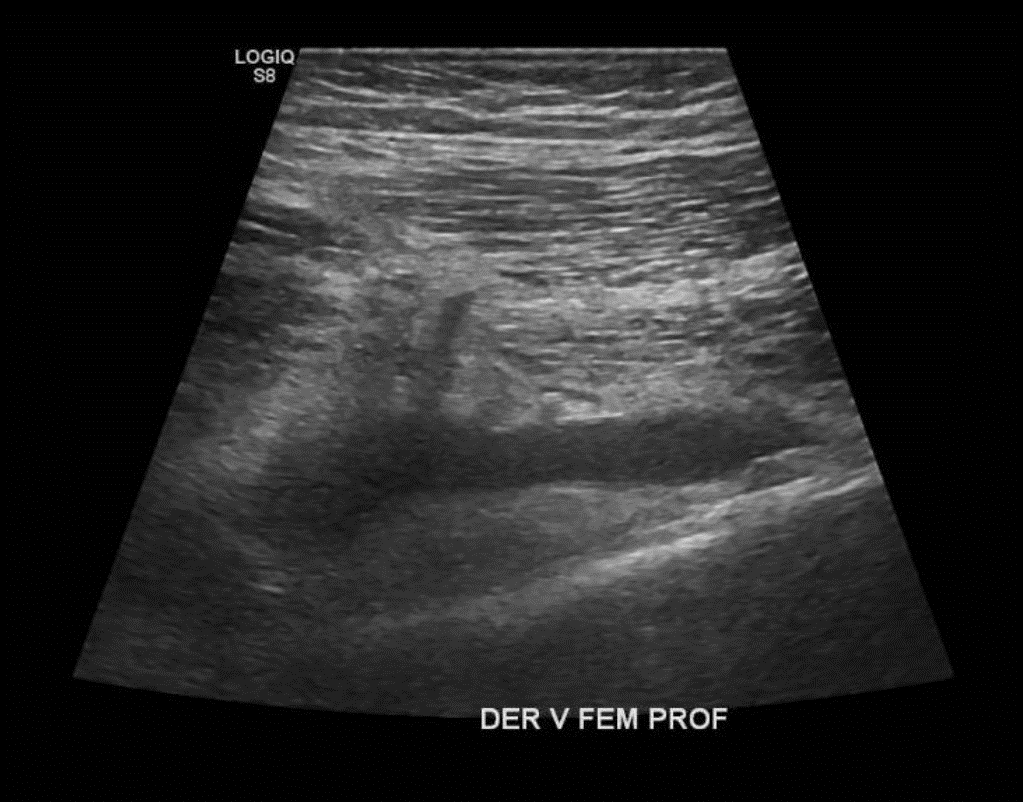

• Desde la VFC se visualiza contenido ecogénico interno, no compresible y sin señal al Doppler Color sugerente de Trombo que se extiende por toda la cara posterior del muslo comprometiendo a la Vena Femoral Profunda. Vena Femoral Superficial permeable.

Hallazgos: Piel y tejido subcutáneo sin alteraciones. Material ecogénico endoluminal en vena femoral común, vena femoral superficial y profunda, con ausencia de flujo y compresibilidad, compatible con trombosis venosa profunda en evolución. Planos musculares de aspecto ecográfico conservado, sin evidencias de desgarros fibrilares. Engrosamiento disminución de ecogenicidad inserción proximal de los isquiotibiales, sin desgarros. No se observan lesiones nodulares ni quísticas. Contornos óseos visualizables regulares. Impresión

Diagnóstico: Hallazgos compatibles con trombosis venosa profunda de vena femoral común, vena femoral superficial y profunda. Es indispensable evaluación clínica de urgencia. Entesitis proximal de los isquiotibiales.